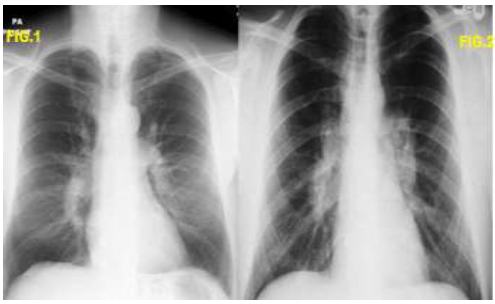

Na radiologia torácica há um achado clássico denominado de Tríade de Garland ou sinal do 1,2,3. (figura abaixo). Esses achados se referem ao alargamento mediastinal (paratraqueal direita, normalmente) e hilar bilateral (gânglios hilares).

Analise as duas imagens abaixo e assinale a alternativa correta: